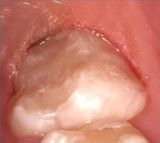

- Allungamento di corona

Applicazioni Cliniche